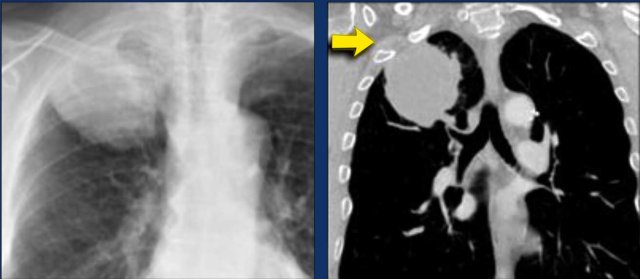

N3 Nodes

N3-nodes represent contralateral mediastinal or contralateral hilar lymphadenopathy or scalene or supraclavicular nodes.

This is considered irresectable disease.

Image

Right sided tumor with N3 lymph node metastases, including the contralateral mediastinal 4L and 5 station.

These images are of two different patients with lung cancer in the right lung.

Images

There are lymph nodes on the contralateral side.

If these lymph nodes contain tumor cells, it means N3 disease.